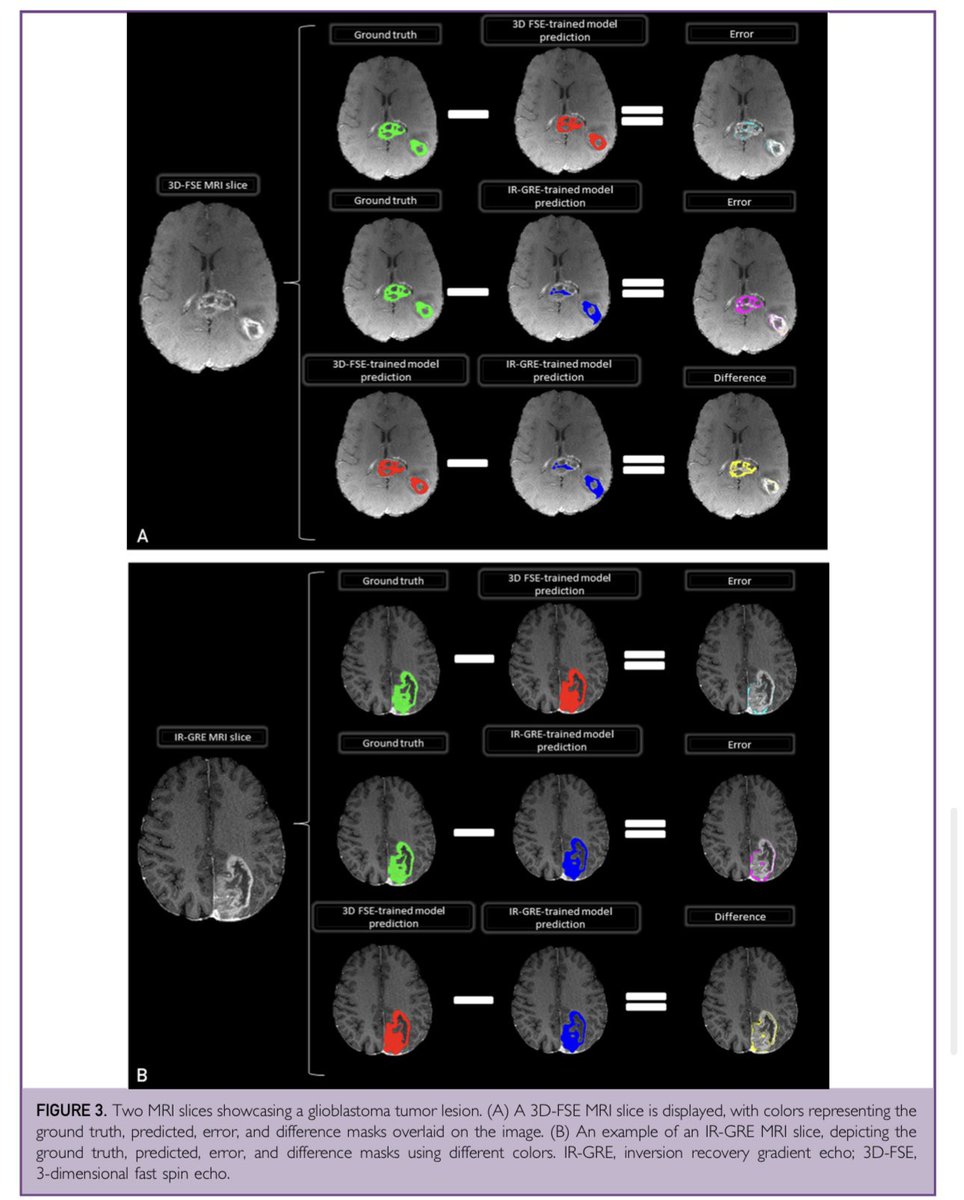

In our recent publication, we explored how adding heterogeneity in the training set helps #glioblastoma tumor #segmentation generalization! https://t.co/4q7PFxbBY7 Thanks to @ShahriarFaghani and @giemmecci and special thanks to my amazing mentor @Slowvak!